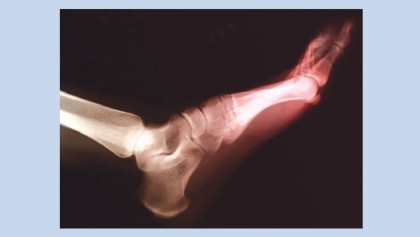

Gout symptoms often first appear in the big toe. Symptoms can include intense joint pain and swelling.